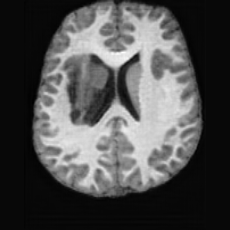

PathologicalHealthyDifferencew/o ACGw/ ACG(a)Refer to captionRefer to captionRefer to captionRefer to captionRefer to captionHealthyPathologicalDifferencew/o ACGw/ ACG(b)Refer to captionRefer to captionRefer to captionRefer to captionRefer to caption

Figure 6: Ablation study of Anatomy Consistency Guidance (ACG): (a) pathology-to-healthy; (b) healthy-to-pathology. Without ACG, edits cause anatomical inconsistencies outside lesions (arrows), whereas ACG keeps modifications lesion-focused.

Anomaly Consistency Guidance. Fig. 6 demonstrates the effectiveness of the proposed Anatomy Consistency Guidance (ACG) on bidirectional editing. Without ACG, the generated brains exhibit noticeable and unrealistic anatomical deformations in non-lesion regions (arrow-indicated), leading to structural inconsistencies between the edited and original brains, as shown in the corresponding difference maps. After incorporating ACG, the model effectively constrains editable modifications within pathological regions, while preserving the remaining anatomy. Tab. 4 further reports their quantitative performances: removing ACG leads to a substantial degradation in all L1, PSNR, and SSIM scores, reaffirming the critical role of ACG in achieving more accurate and structurally consistent reconstructions.

Table 4: Quantitative result of ablation study on Anomaly Consistency Guidance (ACG) for pathology-to-healthy editing.

Dataset Method L1 (\downarrow) PSNR (\uparrow) SSIM (\uparrow)

HCP [39]

w/o ACG 0.025 25.56 0.835

w/o ACG 0.009 32.31 0.967

ADHD200 [5]

w/o ACG 0.238 26.14 0.826

w/o ACG 0.008 33.25 0.968

OASIS3 [26]

w/o ACG 0.026 25.10 0.849

w/o ACG 0.007 33.56 0.980